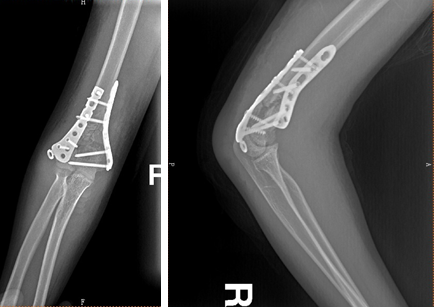

39岁男性,车祸伤

术前

术后